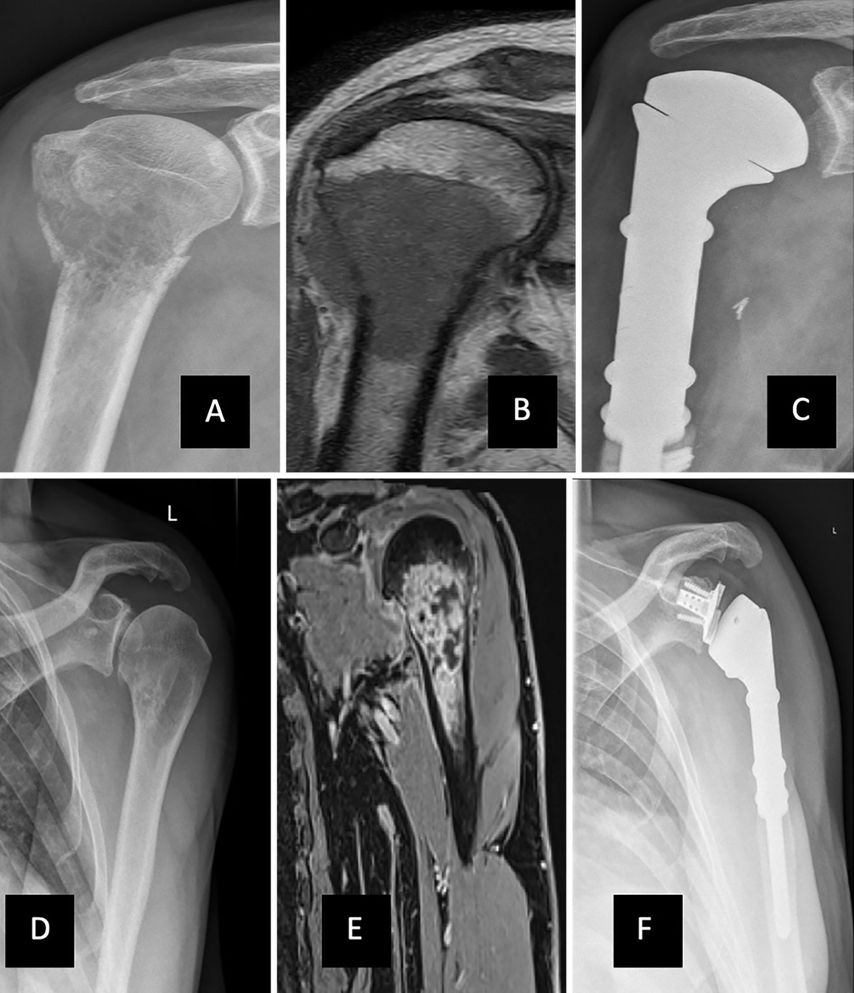

Nach erfolgter Tumorresektion sind meist umfassende rekonstruktive Verfahren notwendig.4,6,7 Nebst dem Einsatz von Tumorprothesen als Ersatz des Knochendefekts (Abb.1) kommen bei Kindern z.B. biologische Rekonstruktionen (z.B. gefäßgestielte Fibula oder bei kleineren Defekten Clavicula-pro-humero-Operation) zur Anwendung.5,7,9 Aus vorangegangenen Publikationen gehen jedoch hohe Komplikationsraten bei der Verwendung von Allografts oder Kompositallografts hervor, wodurch deren Verwendung zur Rekonstruktion nicht uneingeschränkt angeraten werden kann.6–10 Daher hat sich der Einsatz von modularen Prothesen zur Rekonstruktion knöcherner Defekte etabliert und durchgesetzt. Modulare Prothesensysteme (z.B. Mutars® der Fa. Implantcast, Buxtehude, Deutschland) bieten die Möglichkeit, Rekonstruktionslängen in 2cm-Schritten intraoperativ und individuell der Situation anpassen zu können (Abb.2).4 Am Schultergelenk und am proximalen Humerus haben diese Implantate einen geringeren Durchmesser, um eine Weichteildeckung zu erleichtern, und mithilfe eines z.B. Trevira-Anbindungsschlauches kann die Rotatorenmanschette refixiert werden.4–6

Abb. 1: Implantation eines proximalen Humerusersatzes. A) pathologische Fraktur bei Metastase eines Prostatakarzinoms; B) korrespondierende MRT-Bildgebung; C) anatomischer prox. Humerusersatz; D) Röntgenbild mit osteolytischer Raumforderung bei Chondrosarkom; E) korrespondierende MRT-Bildgebung G3; F) inverse Schulterprothese